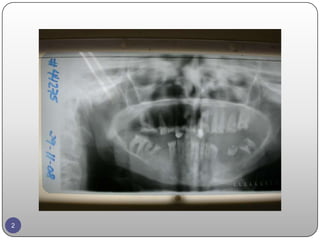

INTRODUCTION  Patient arrivedto the dental center seeking restoring the esthetic and the function of his mouth which is severely deteriorated by his bad history of careless behavior toward his oral hygiene.  He visited and consulted many dentist but he refused the treatment planning by insisting on replacing his missing teeth by FPD and crowning the deteriorated teeth. 4